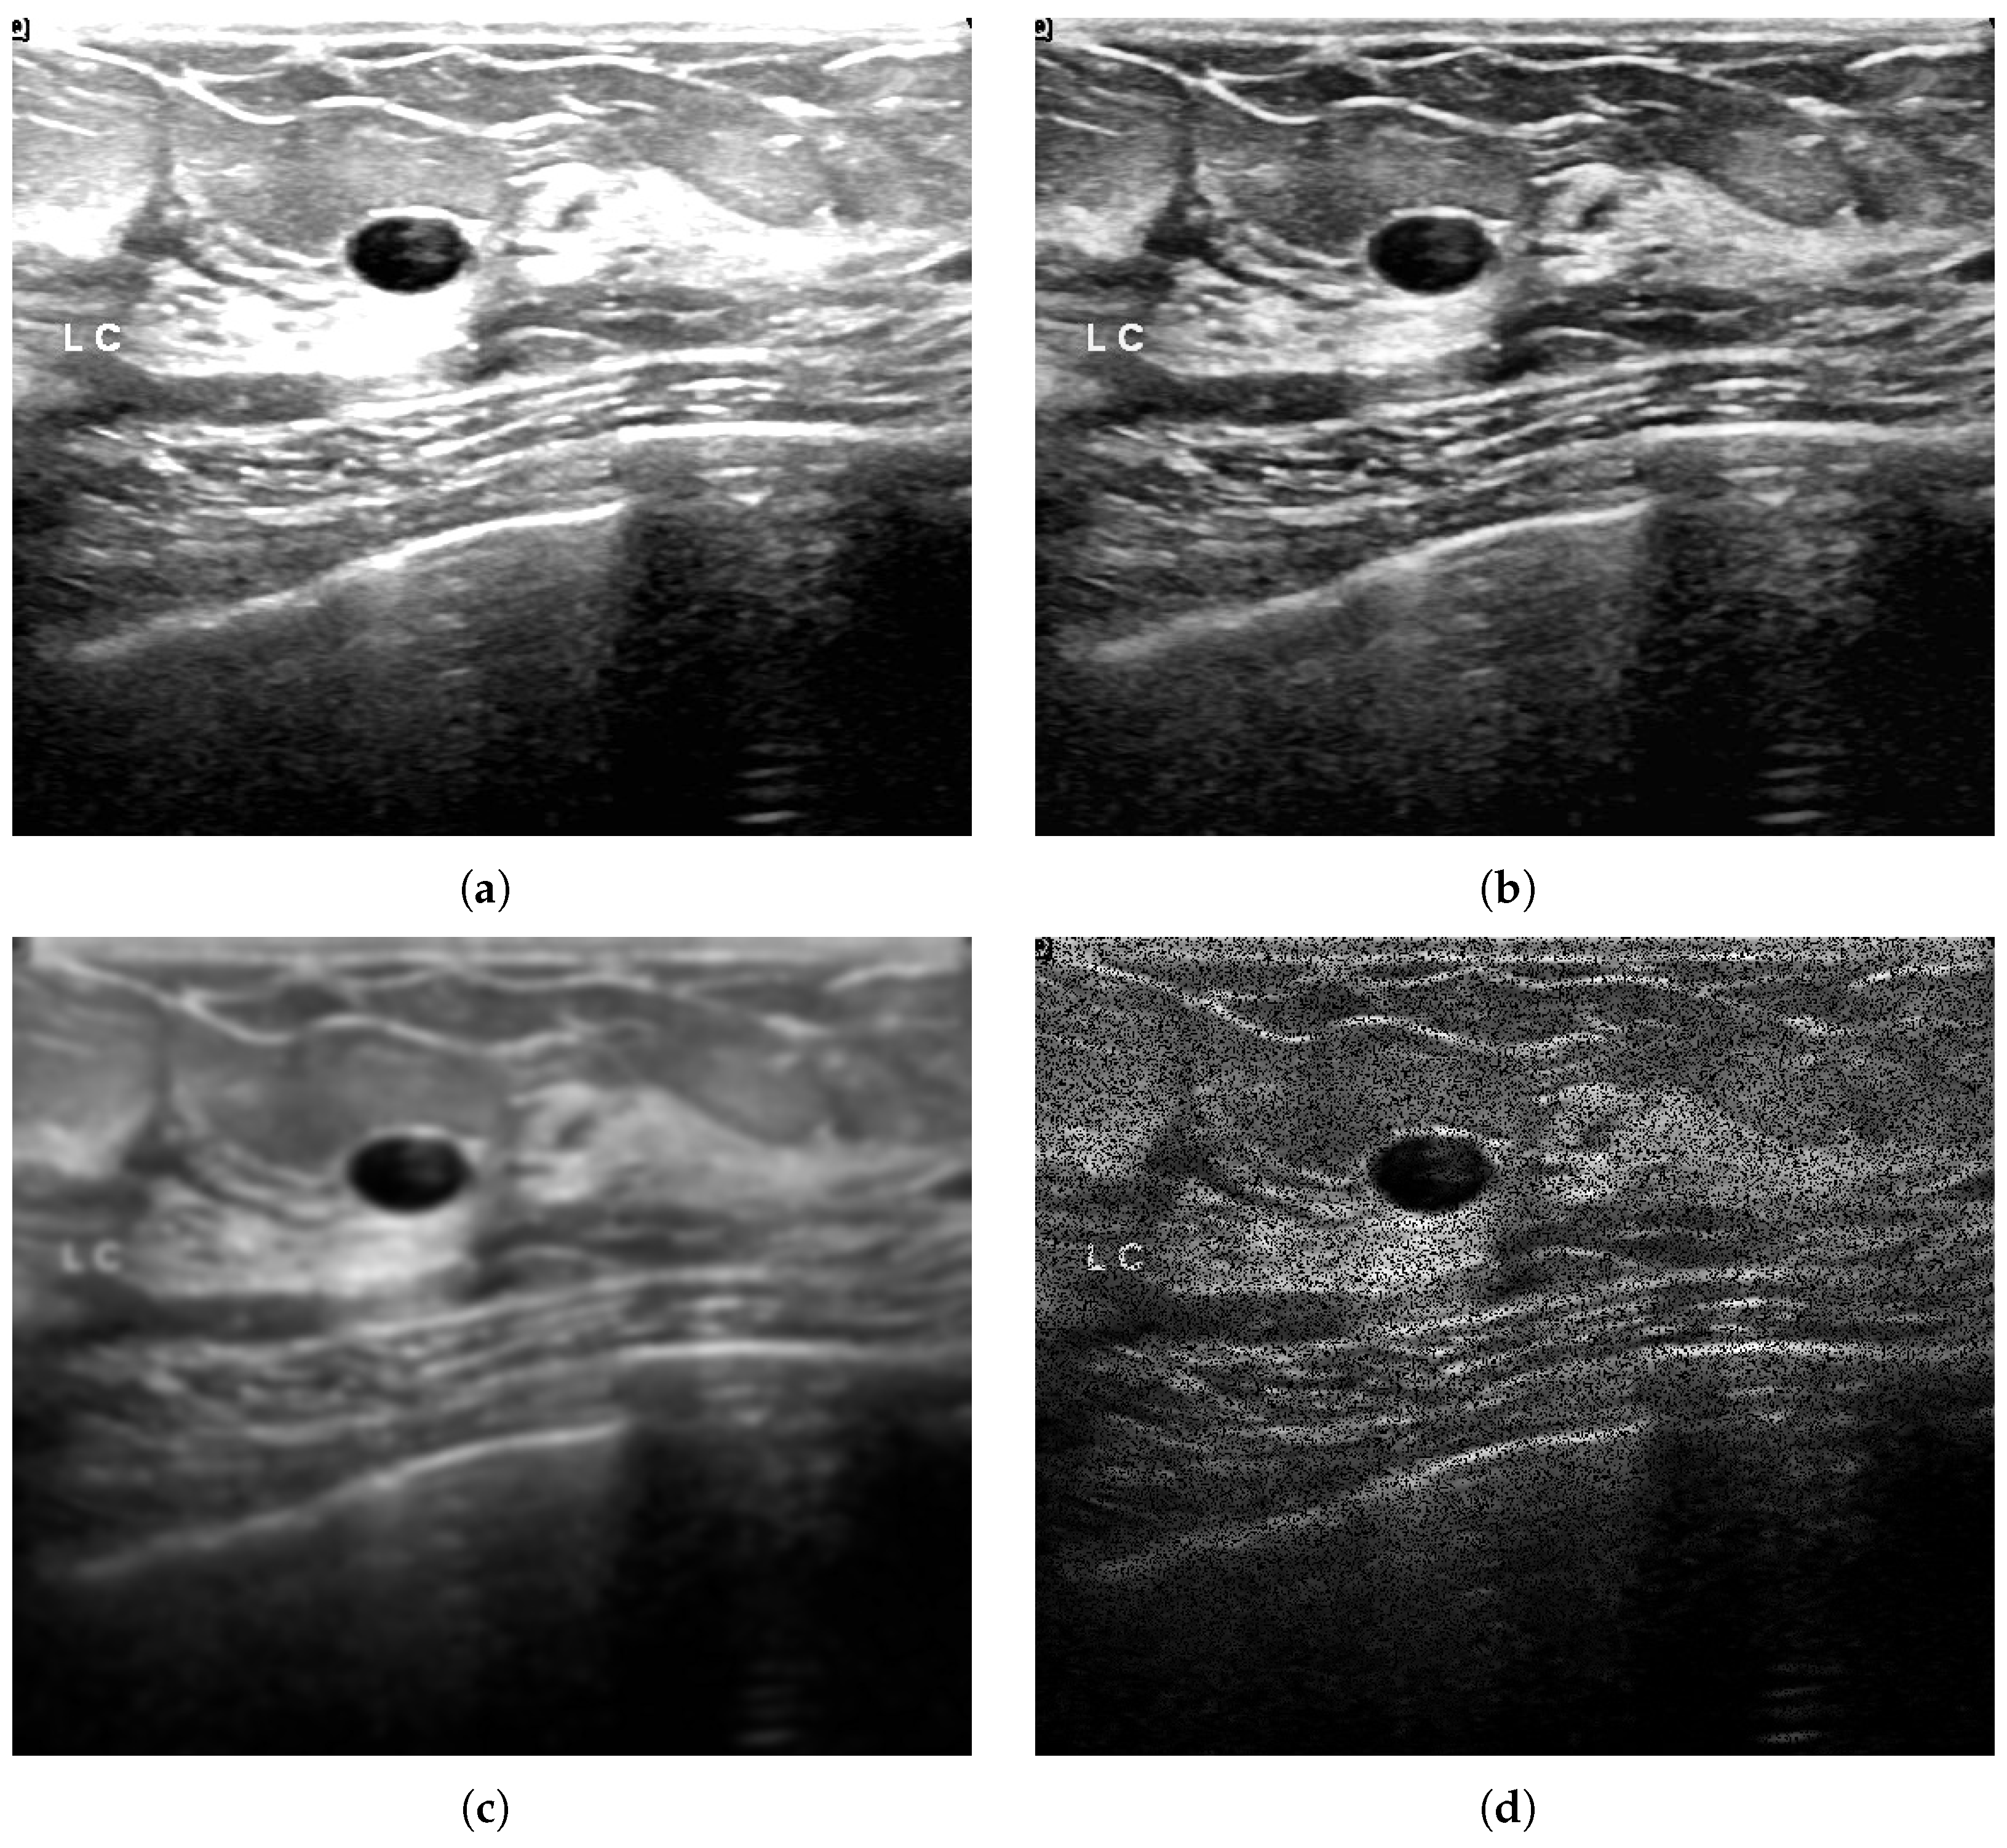

- Sun, Y.; Mogos, G. Impact of visual distortion on medical images. IAENG Int. J. Comput. Sci. 2022, 49, 36–45. [Google Scholar]